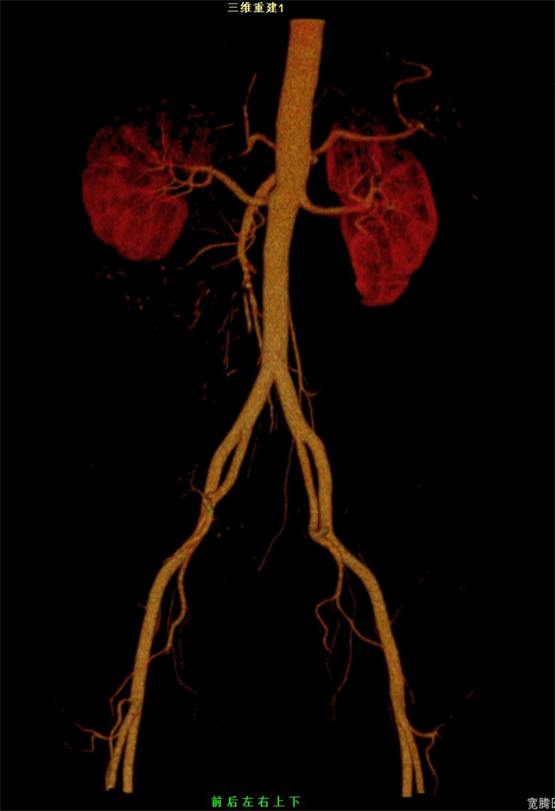

1.常规平扫加增强:宽腾医疗CT系列具有智能追踪和经验值等多种增强扫描方案,定制化血管增强和多期脏器增强扫描解决方案,采用最快0.5秒机架旋转,1.75大螺距扫描,最低70kv低剂量智能毫安调节技术,实现低剂量/低辐射/低对比剂/低速率“四低”临床检查方案,满足临床诊断。

2.急诊以外伤为主:宽腾医疗CT系列采用大孔径设计,急诊外伤患者等特殊体位患者更大包容性,一站式急诊扫描流程,智能摆位,一键建档,最快0.5秒机架旋转,同台多平面重组/3D多序列多算法重建图像,为医生争取抢救黄金时间。

目前,通过对当地其他医院的CT和现已装机的64排128层螺旋CT图像质量进行对比分析发现,两者在扫描范围上有很大差异,这对于提高临床医生对疾病的认识和诊治水平有着十分重要的意义;另外,其相对于普通设备而言具有更大的体量优势和功能优势,使得它能够满足不同病人的需求。同时,对心脏成像、脑血管综合解决方案、血管成像、肺结节检查及结肠病变普查等多项科研技术实现了重大突破。